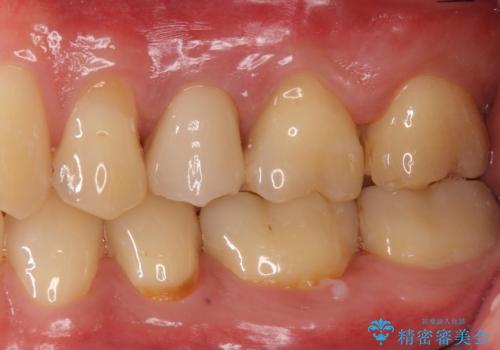

根管内の感染源を可能な限り除去し洗浄しました。

術後は腫れがなくなり特に症状も出ず、メンテナンスに移行しました。